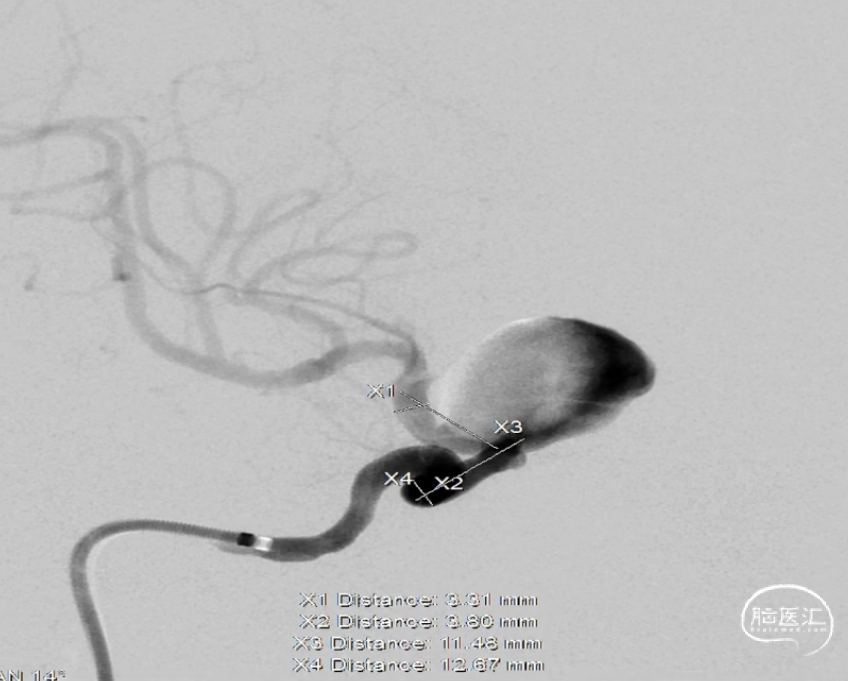

术前测量

动脉瘤:长:20.98mm;宽:17.13mm;高:19.08mm;典型颅内动脉大动脉瘤征。

载瘤动脉:瘤颈远端血管径:3.31mm,瘤颈近端血管径:3.80mm,瘤颈远近端长度:约24mm。